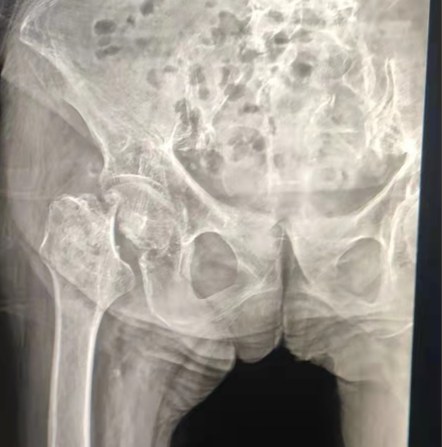

Case Sharing | Un paziente di 70 anni, ha ricevuto la sostituzione totale dell'anca con il sistema dell'anca cementato Lepu

Sistema Cementato dell'anca:

Materiali in lega Co-Cr-Mo

Elevata resistenza all'usura

Grande resistenza meccanica

Design del filo della spalla

Installare, tenere premuto e regolare facilmente l'angolo

Trattamento della superficie lucidata

Per ottenere un eccellente ingrowthGarantire la stabilità della fissazione precoce

12/14 Design conico standard

Proximal Mix Anatomy

Caratteristiche dello stelo della collezione di design in Europa e negli Stati Uniti

Distal Entrambi i lati Adge il trattamento di taglio

Ridurre la pressione nella cavità midollare